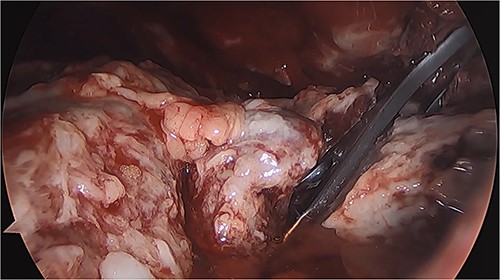

Four days after surgery (12 January 2021), the patient returned due to unrelenting abdominal pain. Thoracic and abdominopelvic tomography was performed, revealing left-sided hydrothorax and leakage from the gastric sleeve into the thoracic cavity. Diagnostic laparoscopy was carried out, but no abdominal leakage site was identified. Additionally, migration of the sleeve through the hiatus was observed, despite the hernioplasty performed during the initial intervention (Fig. 2). Lavage of the cavity, and left pleural drainage were performed.

Laparoscopic image of the second surgery showing the presence of purulent fluid, fibrinopurulent tissue, and migration of the gastric sleeve into the thorax.